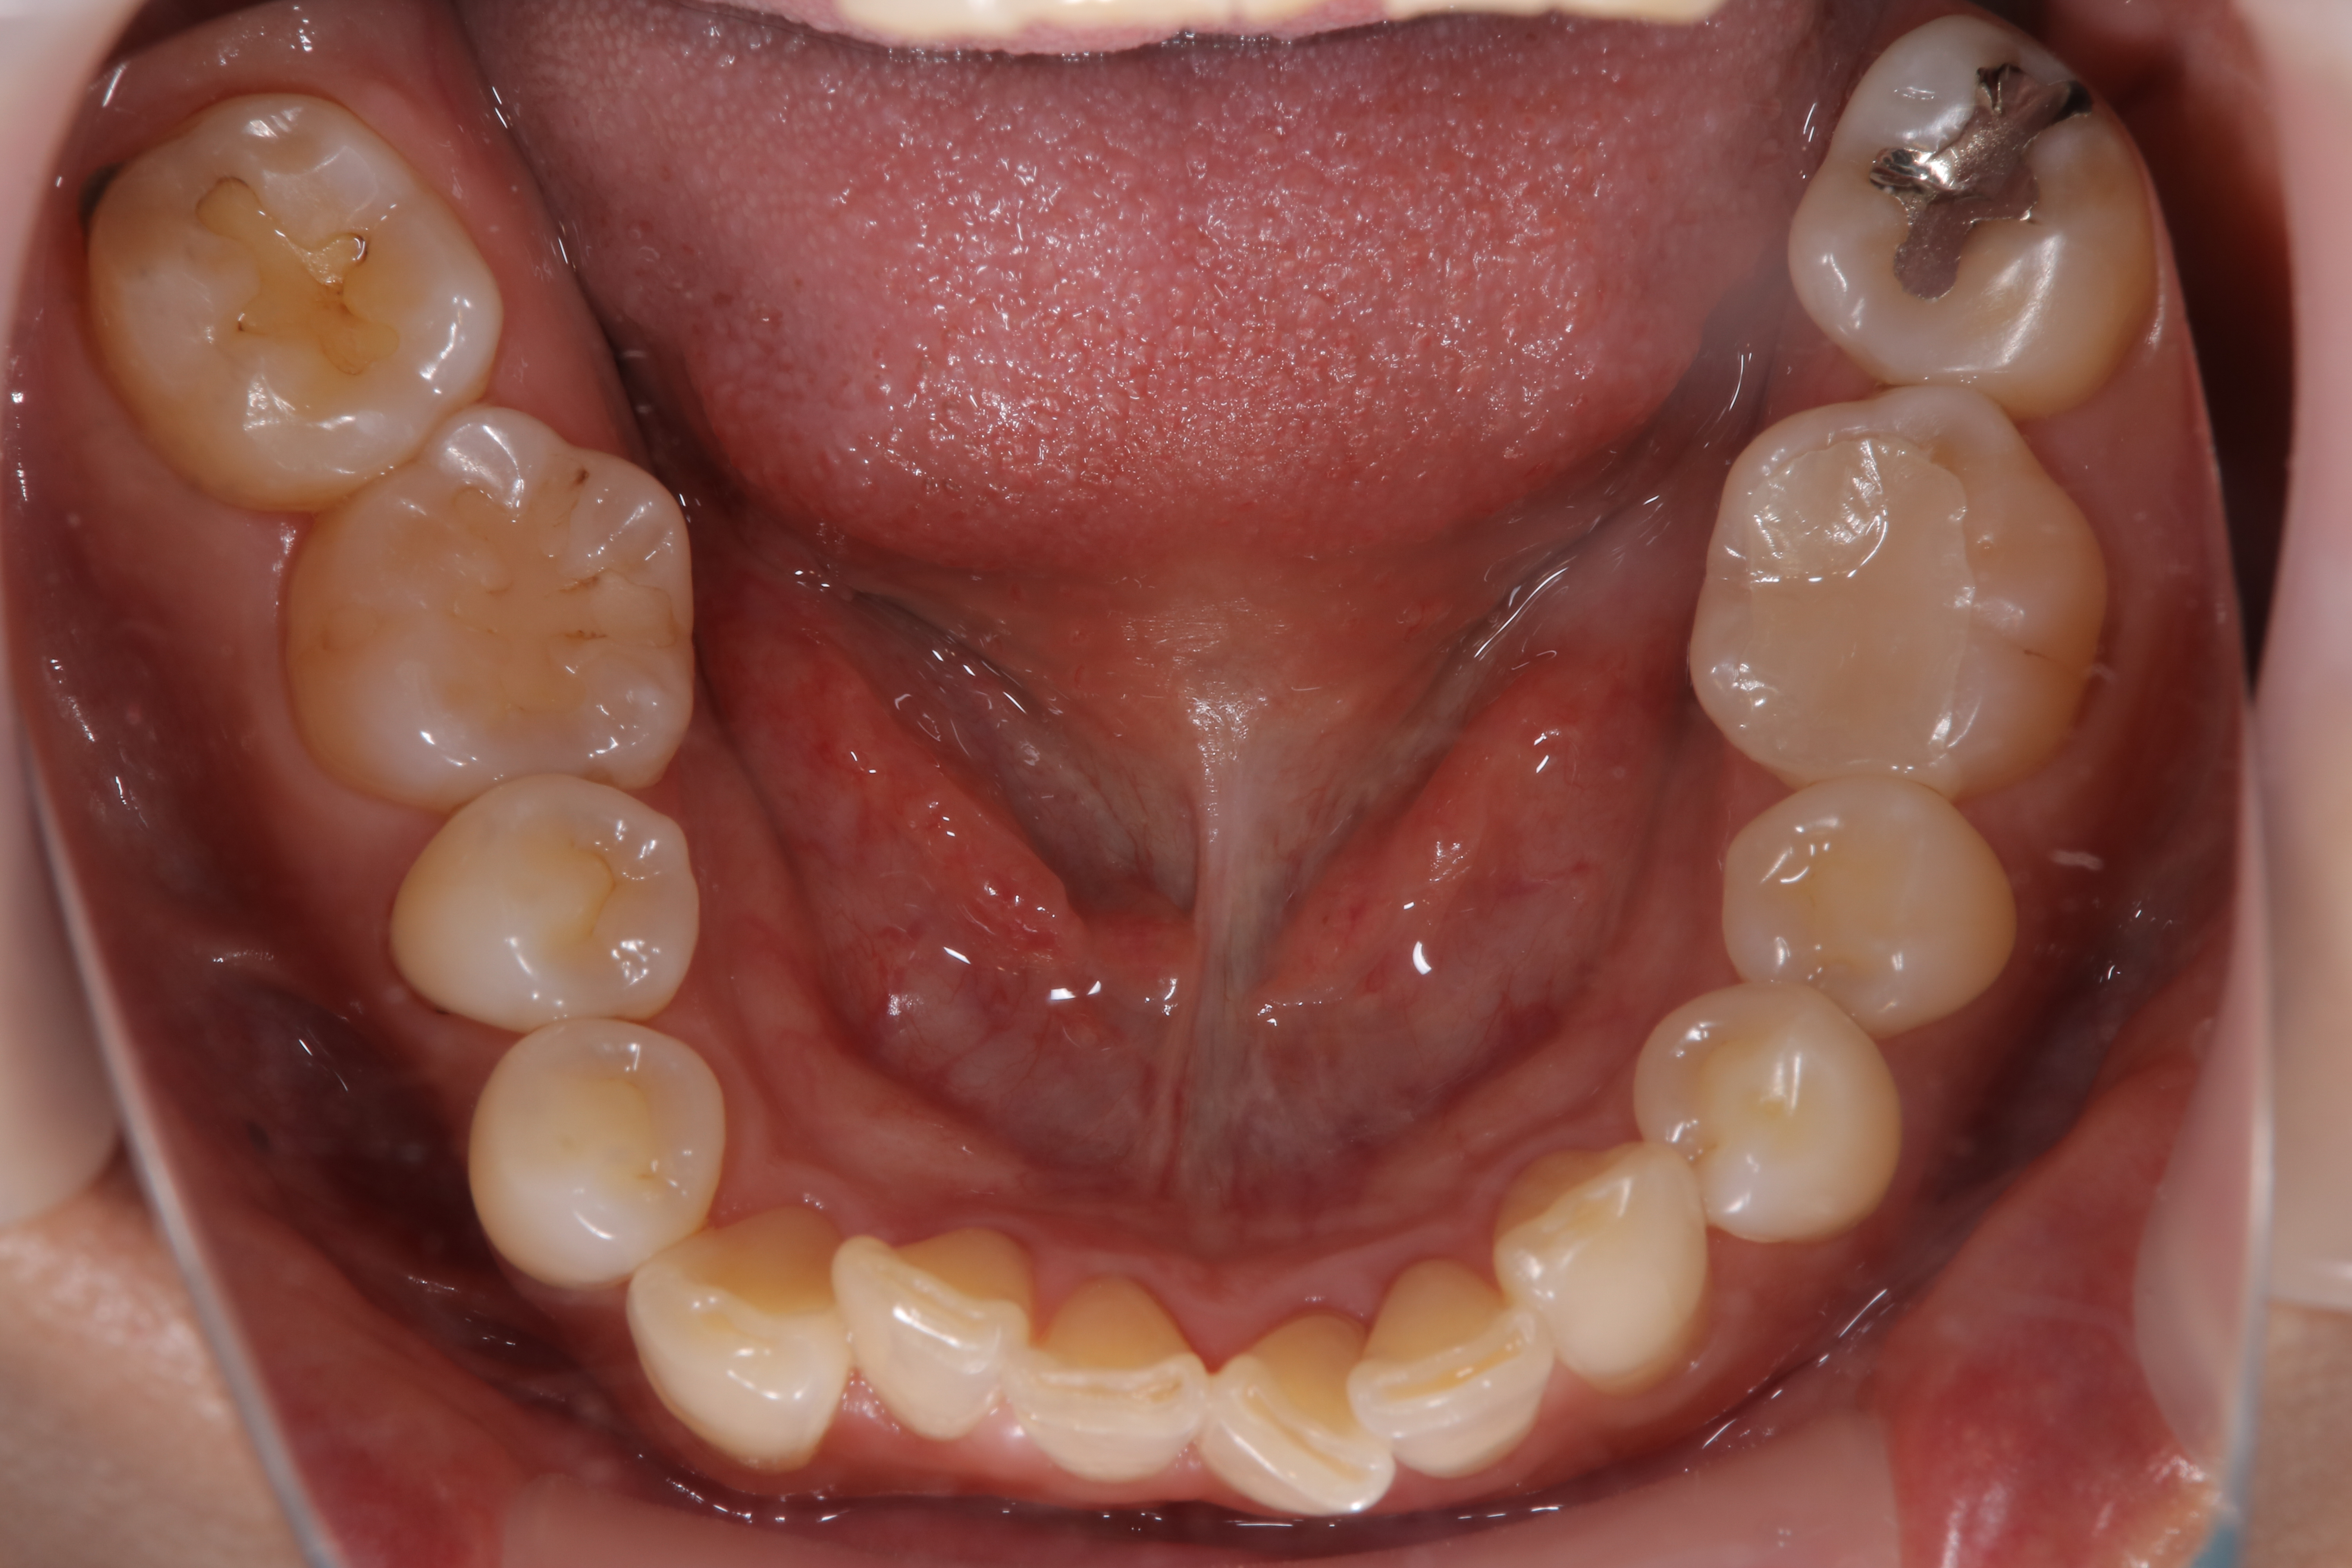

審美歯科治療

症例紹介